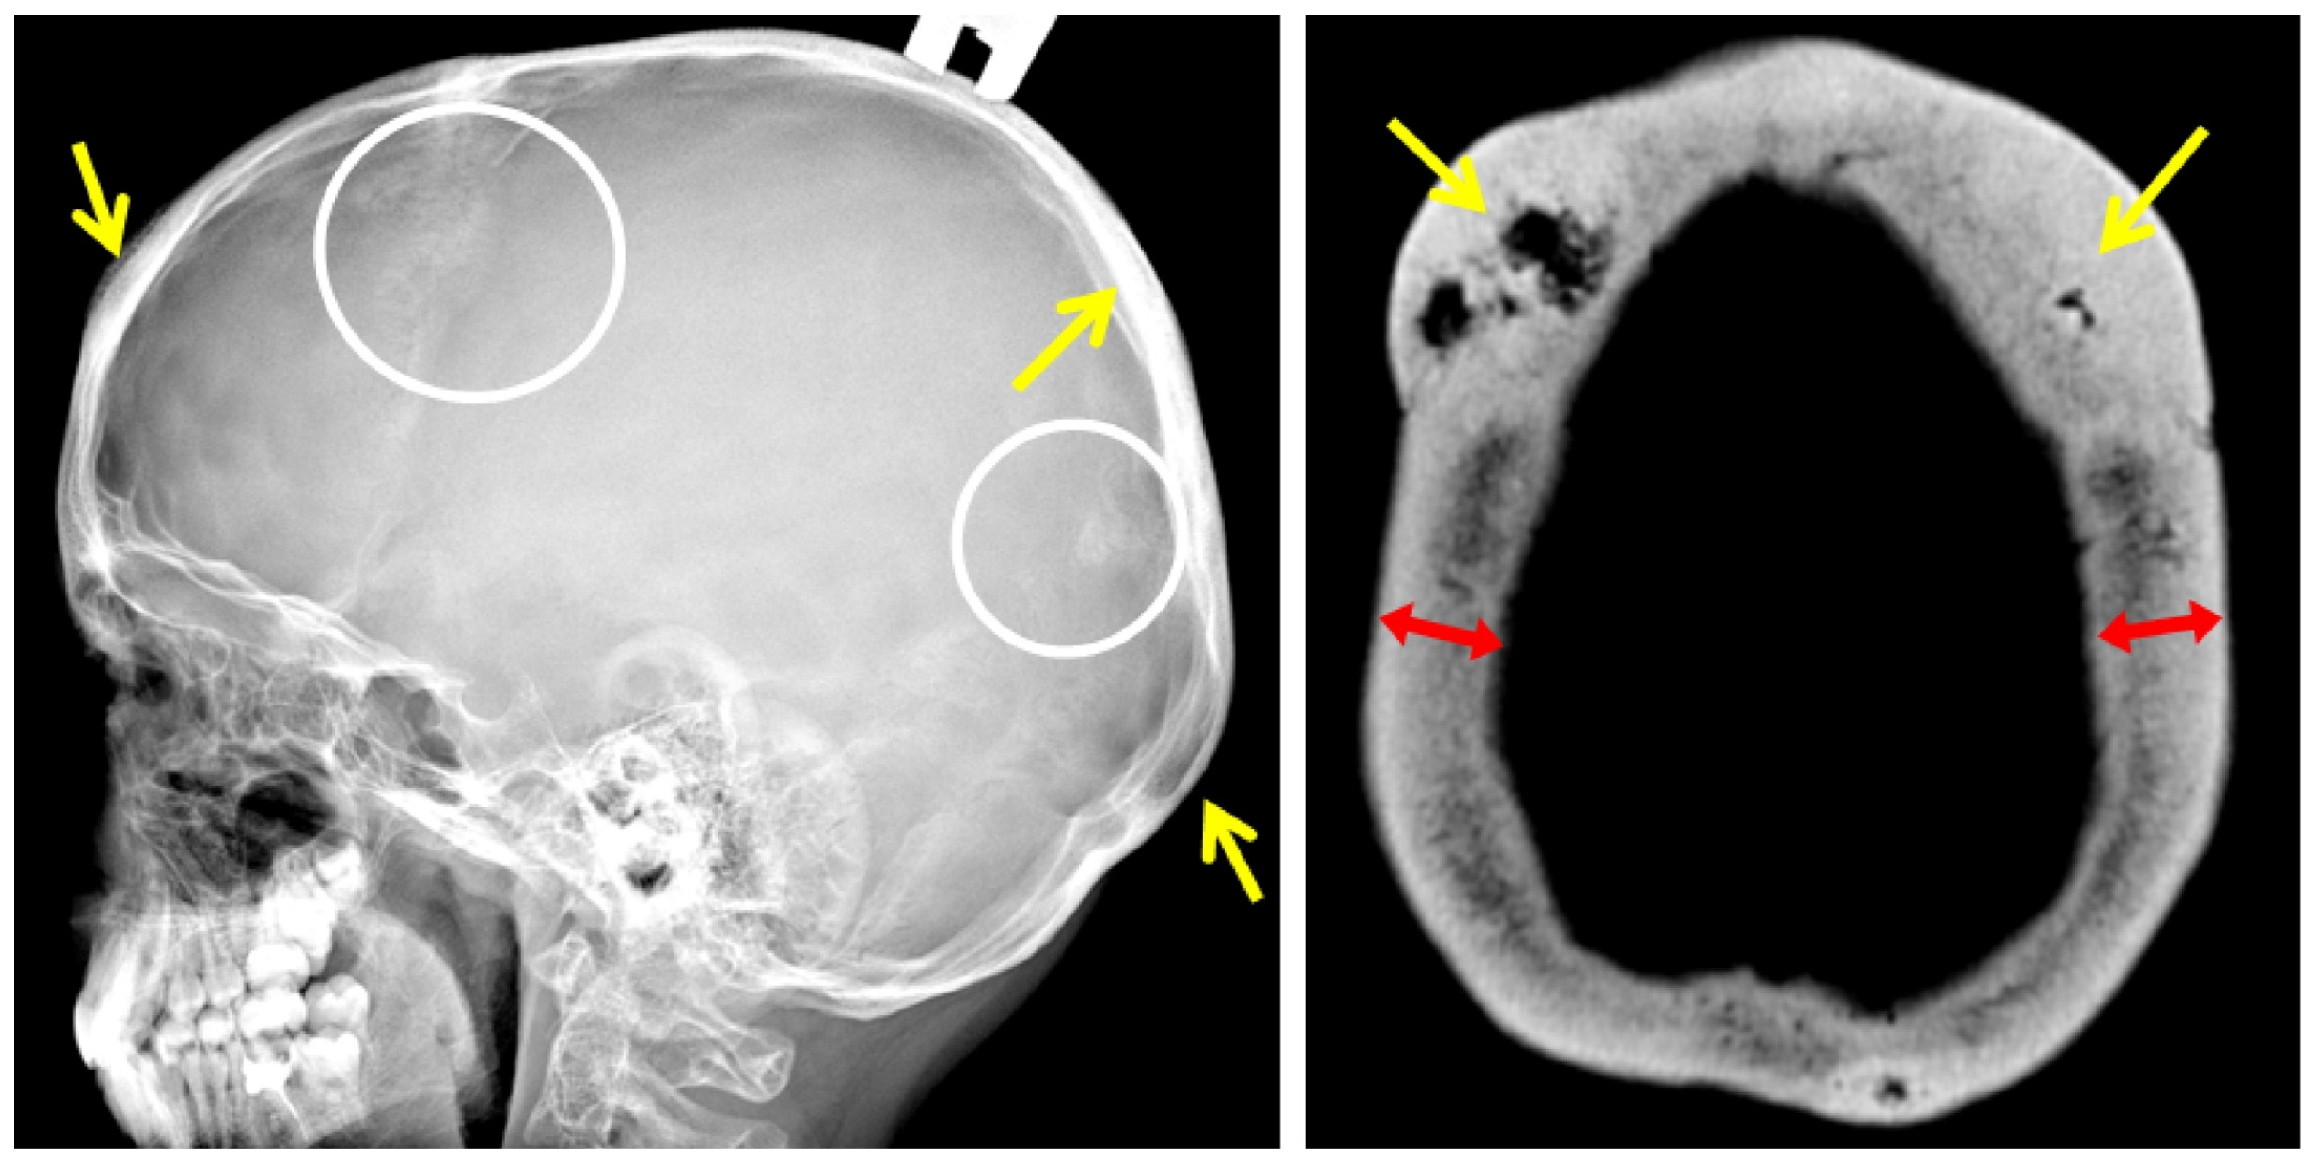

Family 1 is Belarusian and has five affected members in three generations. Proband (III-4) is a 6-year-old boy who started to complain (pointed to where it hurt) of lower back pain from the age of 1 year 7 months, according to his parents. This pain usually lasted from 2 weeks to 1 month and limited the patient’s physical activity, as he was afraid to walk the stairs. Taking into account the increasing lower back pain, an MRI of the thoracolumbar spine was performed at the age of 4 years, which revealed signs of compression fractures of the C7, Th 2-8 vertebral bodies (Figure 2).

Control X-ray densitometry at the age of 6 showed positive dynamics: the BMD of the lumbar spine was 0.357 g/cm2, Z-criterion was −1.9. An X-ray examination of the spine at the age of 6 years revealed diffuse rarefaction of the bone pattern of the vertebrae and a biconcave shape of the thoracic vertebral bodies (Figure 2).

According to the results of the densitometry, all affected family members were diagnosed with severe osteoporosis, and an X-ray examination of the spine revealed signs of compression fractures of the vertebral bodies (Figure 2).

An X-ray examination of the thoracolumbar spine revealed a biconcave appearance of the vertebrae and a wedge-shaped deformity of the vertebral bodies at the entire level of the thoracolumbar spine (Figure 2). During bone scintigraphy of the skeletal system in a 30-year-old individual, no metabolically active zones were detected, which are often found in patients with osteogenesis imperfecta, even outside fracture zones and bone calluses.

Figure 2. Lateral views of the thoracic and upper lumbar spine of the patients of different ages: radiograph of the 6 y.o. boy (F1 III-4) (A)—decreased height and anterior wedging of the vertebral bodies (white arrows), increased height of intervertebral discs (black arrows); T1-weighted MRI of the same patient of the 4 y.o. (B); radiographs of the 12 y.o (F2 II-4) (C) and 30 y.o. (F3 II) (D) patients—severe platyspondyly with accentuated biconcave shape of the vertebral bodies (white dotted lines) and increased height biconvex intervertebral disks (black arrows) more prominent at the thoracic level.